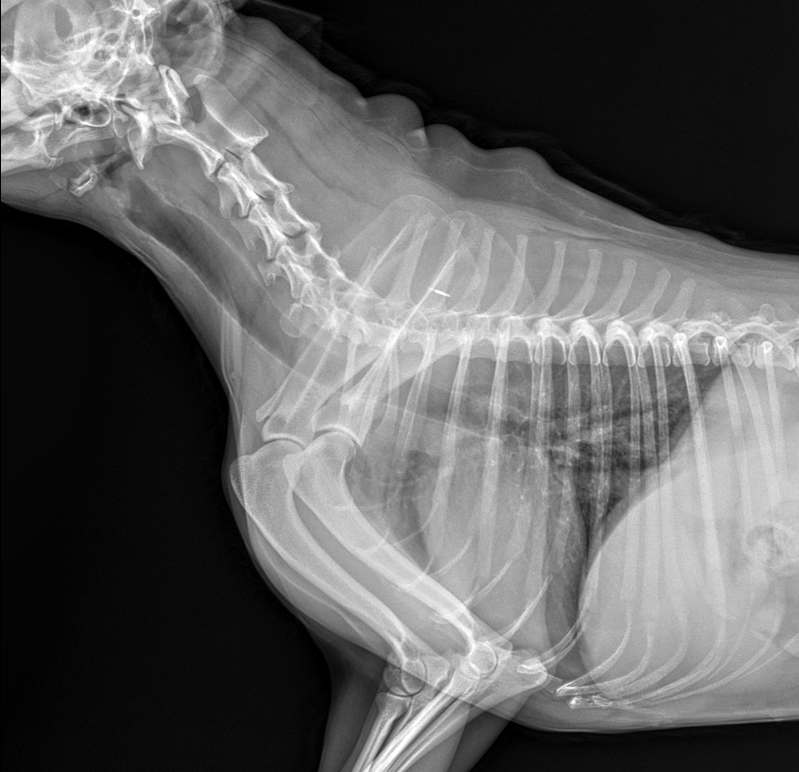

엑스레이 사진도 첨부합니다! 문제점이 뭘까요?

첨부된 사진에서 인후두부의 부종 양상이 경미하게 관찰되나 이를 확인하기 위해서는 전신 마취 후 육안으로 확인하거나 기관 내시경을 통해 확인해 볼 필요가 있으니 주치의와 상의 후에 이상 판단을 받기 위한 검진이 필요합니다.